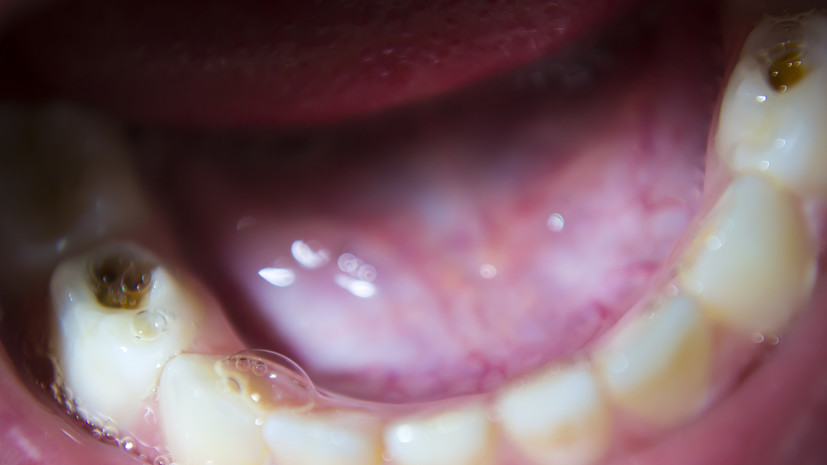

Стоматолог Мартынова: из-за невылеченного кариеса может развиться эндокардит

При множественном кариесе стрептококки направленно провоцируют развитие заболеваний сердечно-сосудистой системы, такие как ревматизм, ишемическая болезнь сердца, инфаркт, инсульт, эндокардит (воспаление внутренней оболочки сердца). Это происходит за счёт особенного строения рецепторов ткани сердца, объяснила она в беседе с «Газетой.Ru».

На этапе начального воспаления развивается пародонтит, что увеличивает вероятность инфекционного эндокардита за счёт постоянного попадания бактерий в кровь, отметила Мартынова.